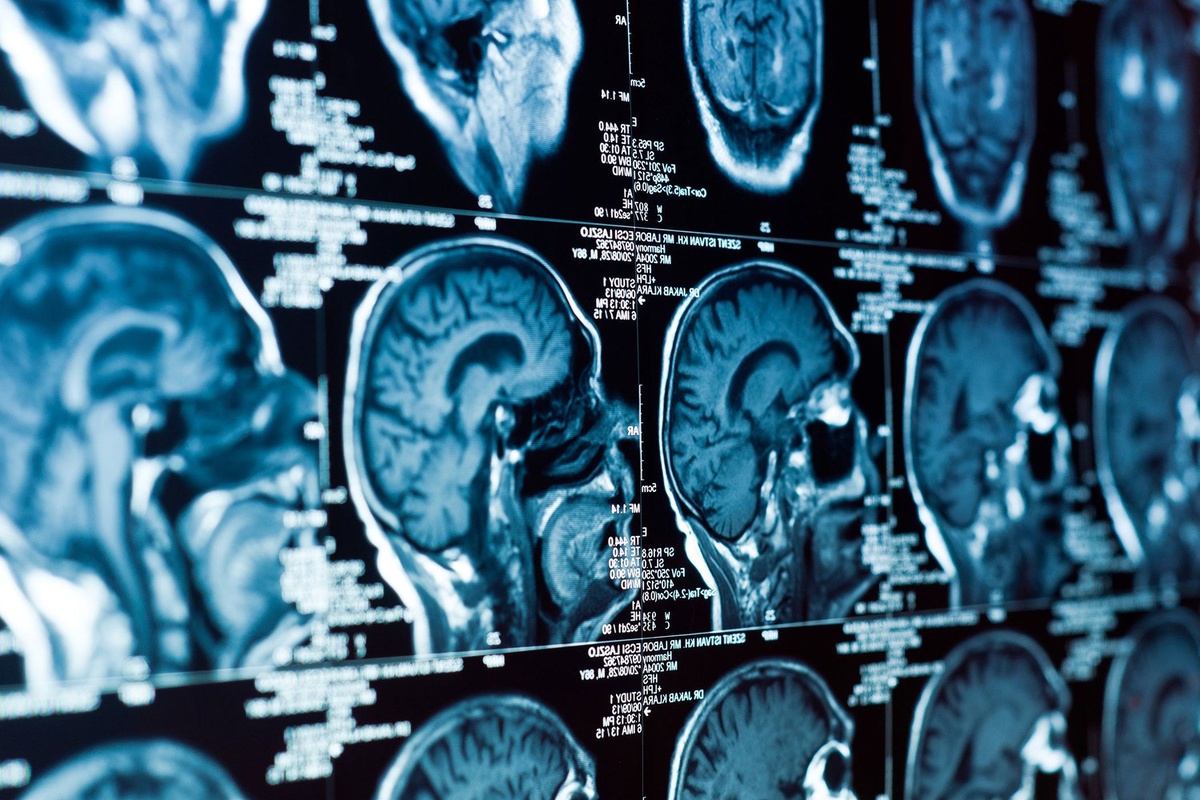

Открытие С. Томаса Кармайкла и Мин Тянь в UCLA Health вселяет надежду на лечение деменции

Ученые выяснили, что воспаление сосудов мозга — главная заварушка в развитии деменции. Они нашли пару молекул, которые как бы «тушат» воспаление, но с возрастом барахлят. На мышках протестировали лекарство от псориаза — и о чудо! Деменция отступила, память вернулась! Пока только на мышках, но надежда на новые лекарства от этой гадости есть!